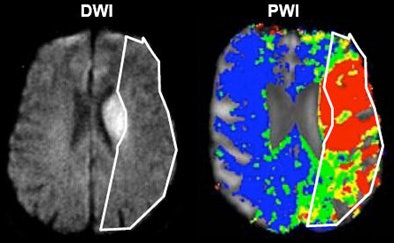

The original penumbra model relied on the mismatch between perfusion and diffusion on MRI -- the mismatched region representing the tissue you want to save, he said. In CT there is no diffusion, only perfusion, which is measured by mean transit time (MTT), cerebral blood flow (CBF), and cerebral blood volume (CBV). The way to distinguish potentially salvageable tissue from the infarct core in CT is by via cerebral blood volume and mean transit time through the cerebral vasculature, he said.

| Acute ischemic stroke visualized on diffusion-weighted MRI (left) and perfusion CT (right). All images courtesy of Dr. Max Wintermark. |